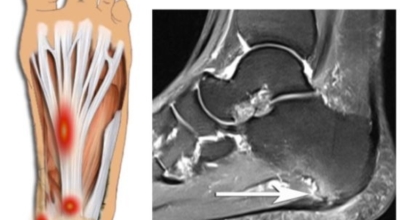

족저 근막염이란?

족저 근막이란 발가락 시작지점부터 발뒤꿈치뼈까지 발바닥 전체를 감싸고 있는 두꺼운 막을 말해요. 족저 근막은 발바닥 아치를 보존시켜 발바닥이 지면을 내딛음으로써 생기는 쇼크을 흡수하는 중요시되는 역할을 수행하고 있어요. 이 족저 근막에 일차적으로 서서히 조직 훼손이 일어나고 계속적인 활동에 의하여 염증이 커지면서 발 뒤꿈치 부근 통증을 일으키게 되는데 염증은 무리하고 반복적인 동작, 많은 활용으로 마찰에 의해 발생해요.

족저 근막염은 염증에 의한 훼손 및 통증을 유발하는 질환인데요 족저 근막염 증상은 동일한 발뒤꿈치 통증 하글런드 병변의 기형으로 알려져 있으고 아킬레스 건과 연관이 깊다고 해요. 특히 근육이 덜 풀린 아침 시간 대는 보행 시 날카롭고 바늘로 찌르는 듯한 심한 통증을 느끼게 된다고 해요. 하지만 아침 시간 대를 지나 오후에 접어들면서 일정 양 통증은 서서히 감소하기 시작한다고 하는데요 초기 증상이 나타난다면 필수로 전문의를 찾아 조기치료하는 것이 바람직해요.